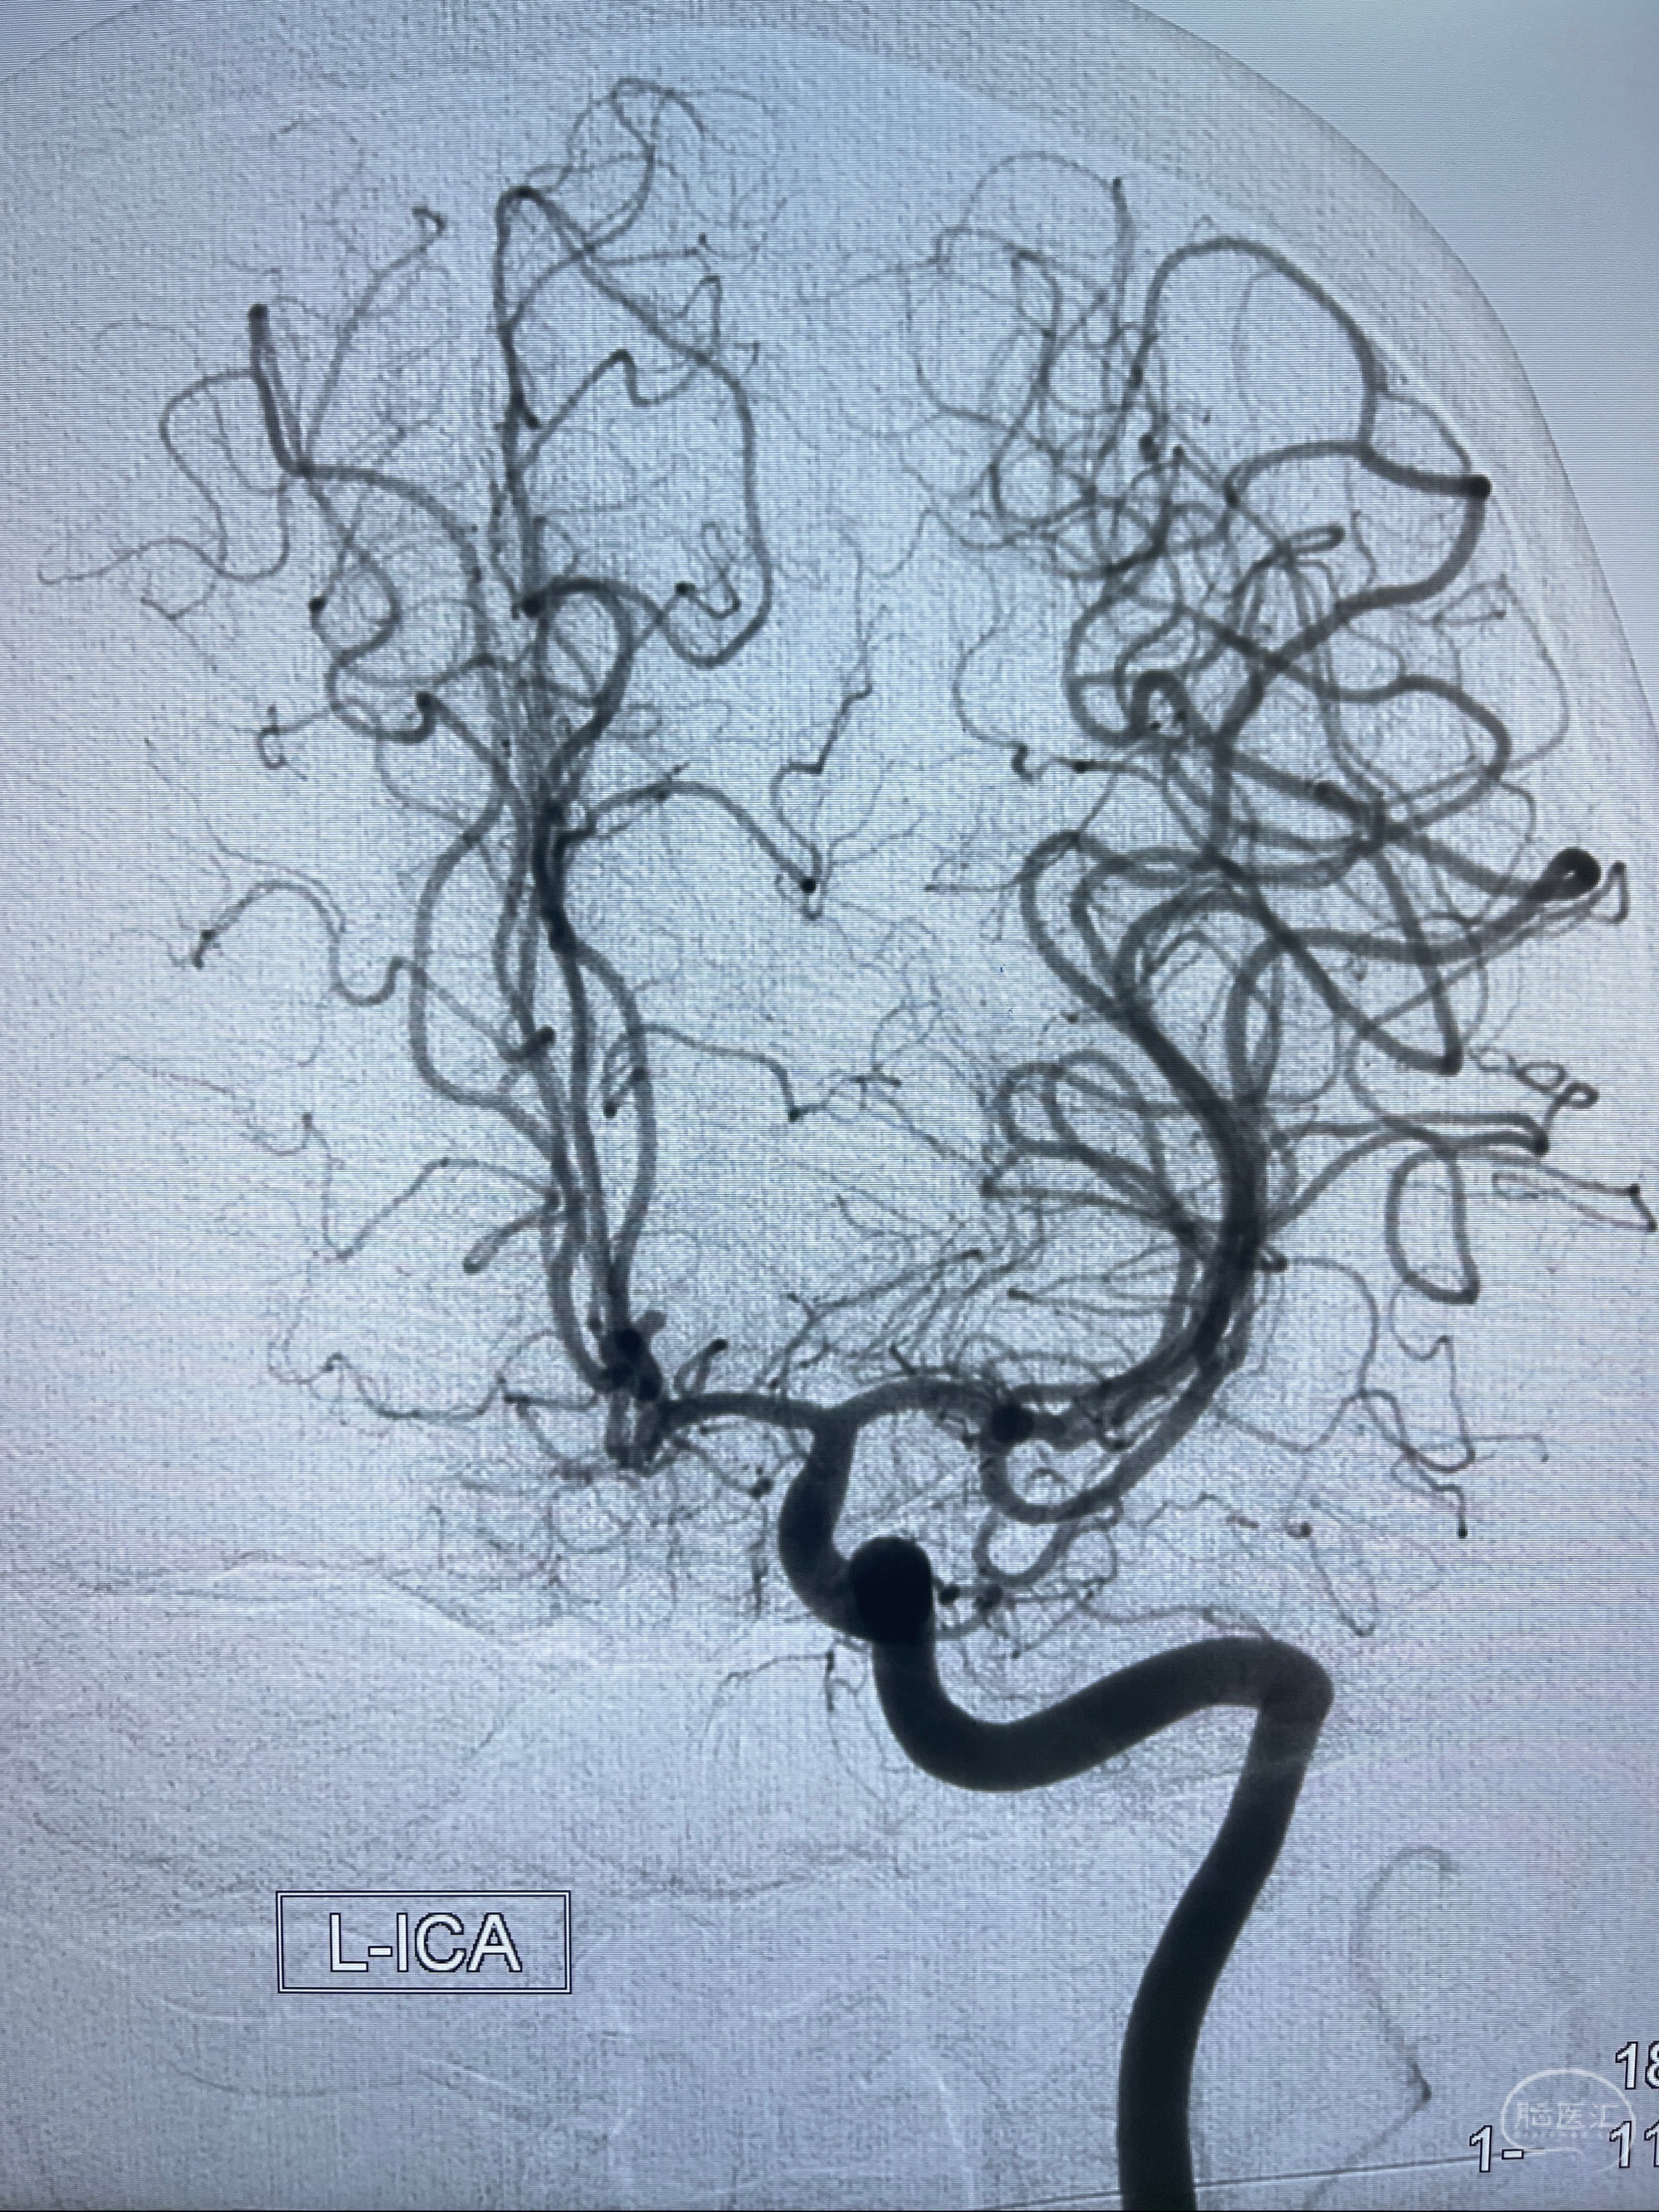

2023-08-23DSA:左侧前交通动脉瘤,左侧A3/4交界处多发动脉瘤